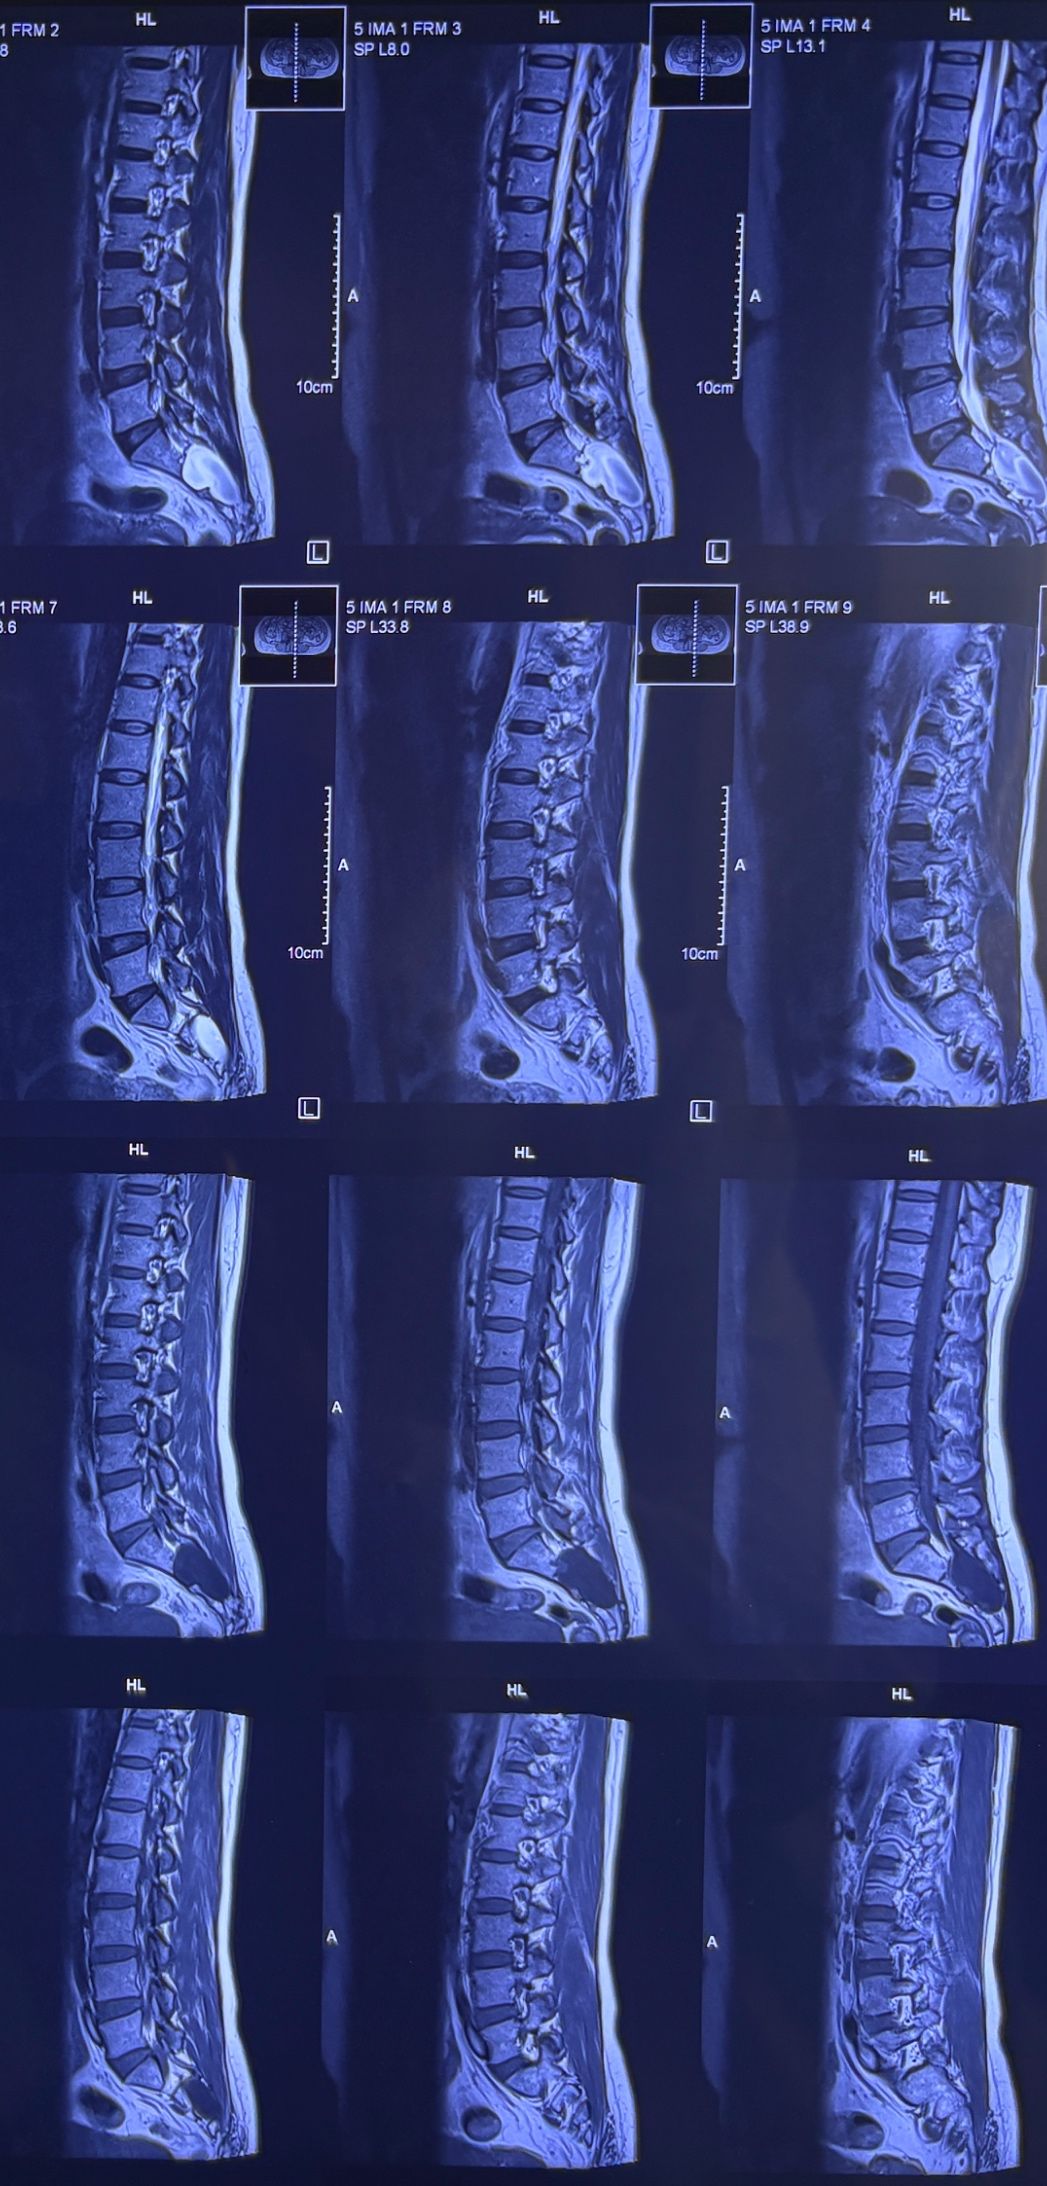

40 yrs old male patient presented to my office who had severe R gluteal pain and radicular pain along R L5-S1 now pain has reduced by 80% in his motor exam had R big toe L5 motor reduced to 4+\5 and R S1 DTR was 0 while L S1DTR was 1+

We did EMG/NCV which showed Mod- sever R L5 S1 irritation without any active axonal loss

I had to decide to refer him for surgery or not patient didn’t have any treatment meanwhile

I ordered new L/S mri

I posted his new mri and old mr

Which was 20 days ago and have posted all below

The first 12 mris had been done 20 days ago

After those first 12 MRIs i have posted new MRIs which were done yesterday

After seeing his new mri and emg/ncv and getting sure his neurological deficit is not active and progressing i told patient he doesn’t need surgery at this time and released him with some advices and exercises

Keep in mind when patient is 80-90 percent pain free and stable i would never give treatment to them just give exercises and follow up their condition